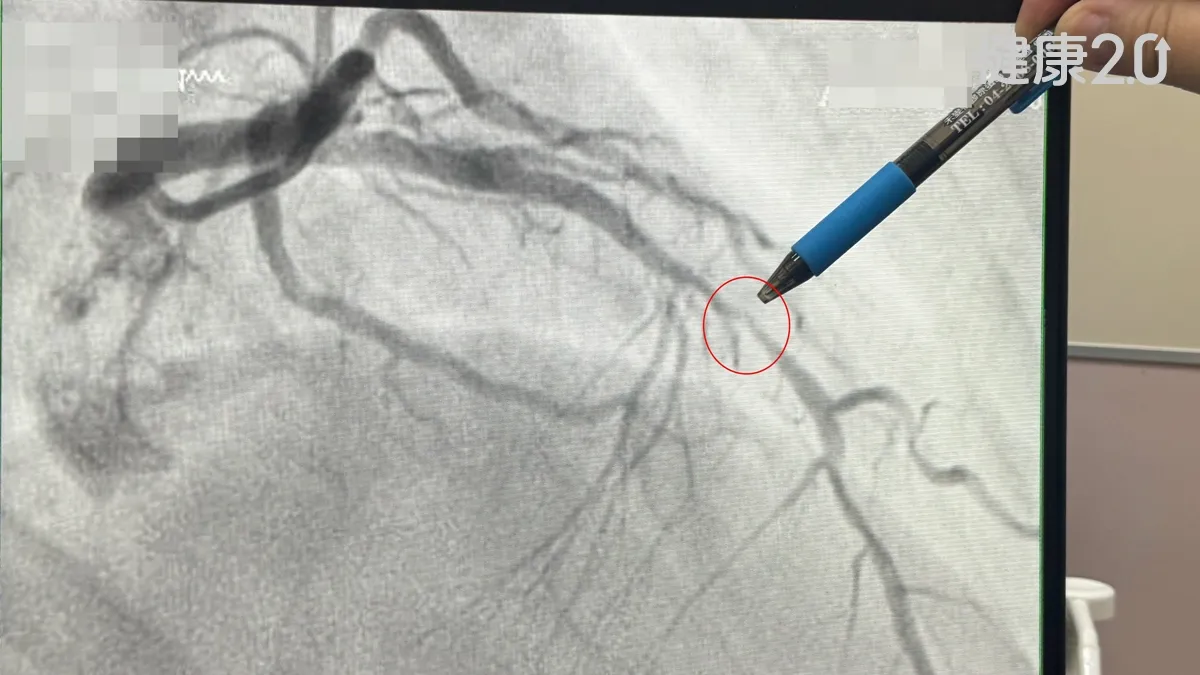

針對肝膿瘍的治療,黃馨慧表示,肝膿瘍患者多數透過抗生素和膿瘍引流2種方式,可達到治療效果,只有極少數病人需要動手術,療程長短與膿瘍的大小及數量等有關;多數肝膿瘍在治癒後並不會復發,但糖尿病人務必妥善控制血糖,以預防各種感染症發生。